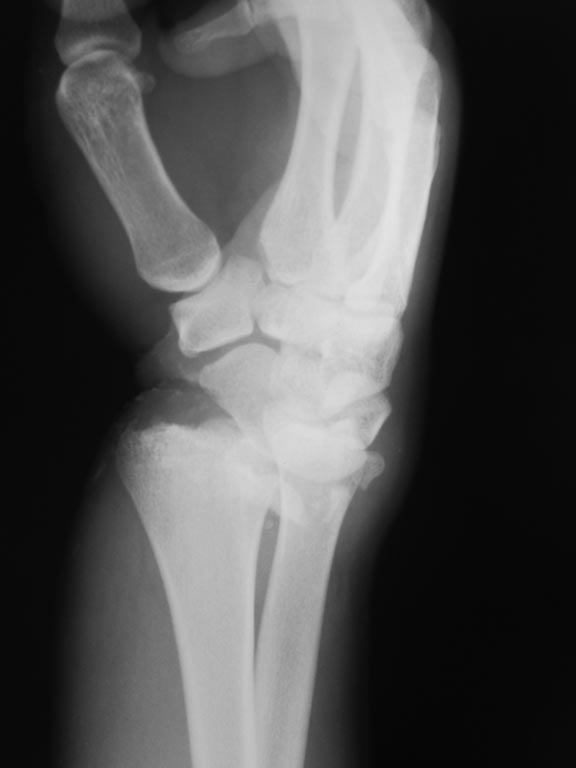

открытый многооскольчатый перелом луча

хотелось бы услышать мнение по дальнейшей тактике лечения. Пациент 23 лет, открытый многооскольчатый перелом дистального эпифиза левой лучевой кости.

Обратился через сутки после травмы, имеется инфицированная рана на ладонной поверхности лучезапястного сустава, выраженный отек. наложен АВФ. Рентгенограммы прилагаются